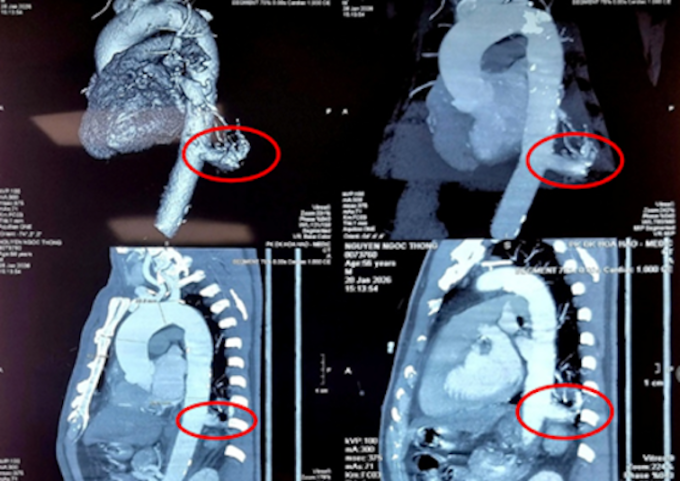

Bác sĩ xác định ở thùy dưới phổi trái của ông có một phần mô phổi phát triển bất thường (kích thước 23×26 mm). Khối mô này không có chức năng hô hấp, không thông với đường thở bình thường mà lại “ăn bám”, nhận máu nuôi dưỡng trực tiếp từ động mạch chủ ngực xuống. Đáng chú ý, nhánh động mạch nuôi khối phổi thừa này có đường kính lên tới 17 mm – kích thước rất lớn và chực chờ vỡ bất cứ lúc nào.

Hình ảnh phần phổi dư thừa của bệnh nhân trên phim chụp. Ảnh: Bệnh viện cung cấp